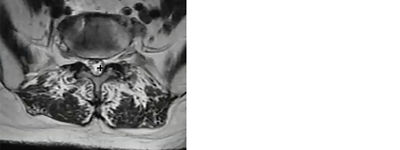

Identifying anatomical landmarks in a mild® patient

Photo Courtesy of James Lynch, PA – L3/L4 interspace

1. Vertebral Body

2. Central Canal

3. Epidural Fat

4. Ligamentum Flavum

5. Spinous Process

6. Exiting Nerve Root Space Under Pedicle Facet Joint

7. Facet